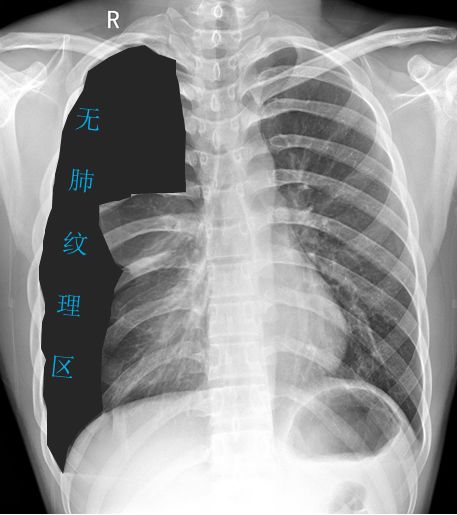

病例2患者的X线胸片

黑色区域:无肺纹理区域。肺叶压缩约70%;

蓝色虚线:被压缩肺组织边缘;

紫色箭头:肋膈角可见液-气平面;

橙色实线:第3、4肋骨前端骨桥关节,肋骨骨桥(先天变异);

可见心影及纵隔向对侧轻度移位。